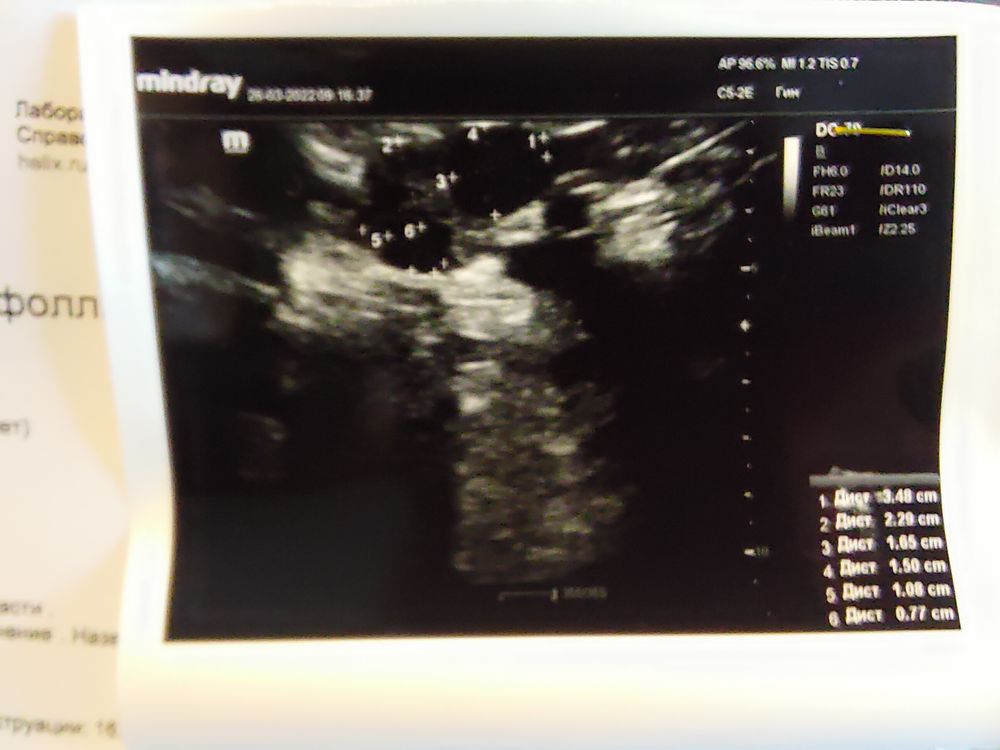

Девочки, кто разбирается в УЗИ?

Помогите, пожалуйста, правильно понять результаты УЗИ.

Сделала УЗИ на 11 ДЦ.. врач сказала дф 18 мм и жидкость в позадиматочном пространстве.

Я её спросила, а может это это быть жт? Она сказала, что пожалуй нет.

Но откуда могла взяться жидкость, если овуляции ещё не было? 4 дня до этого УЗИ жидкости не было.

И эндометрий был 7 стал 10. Мог так вырасти за 4 дня?